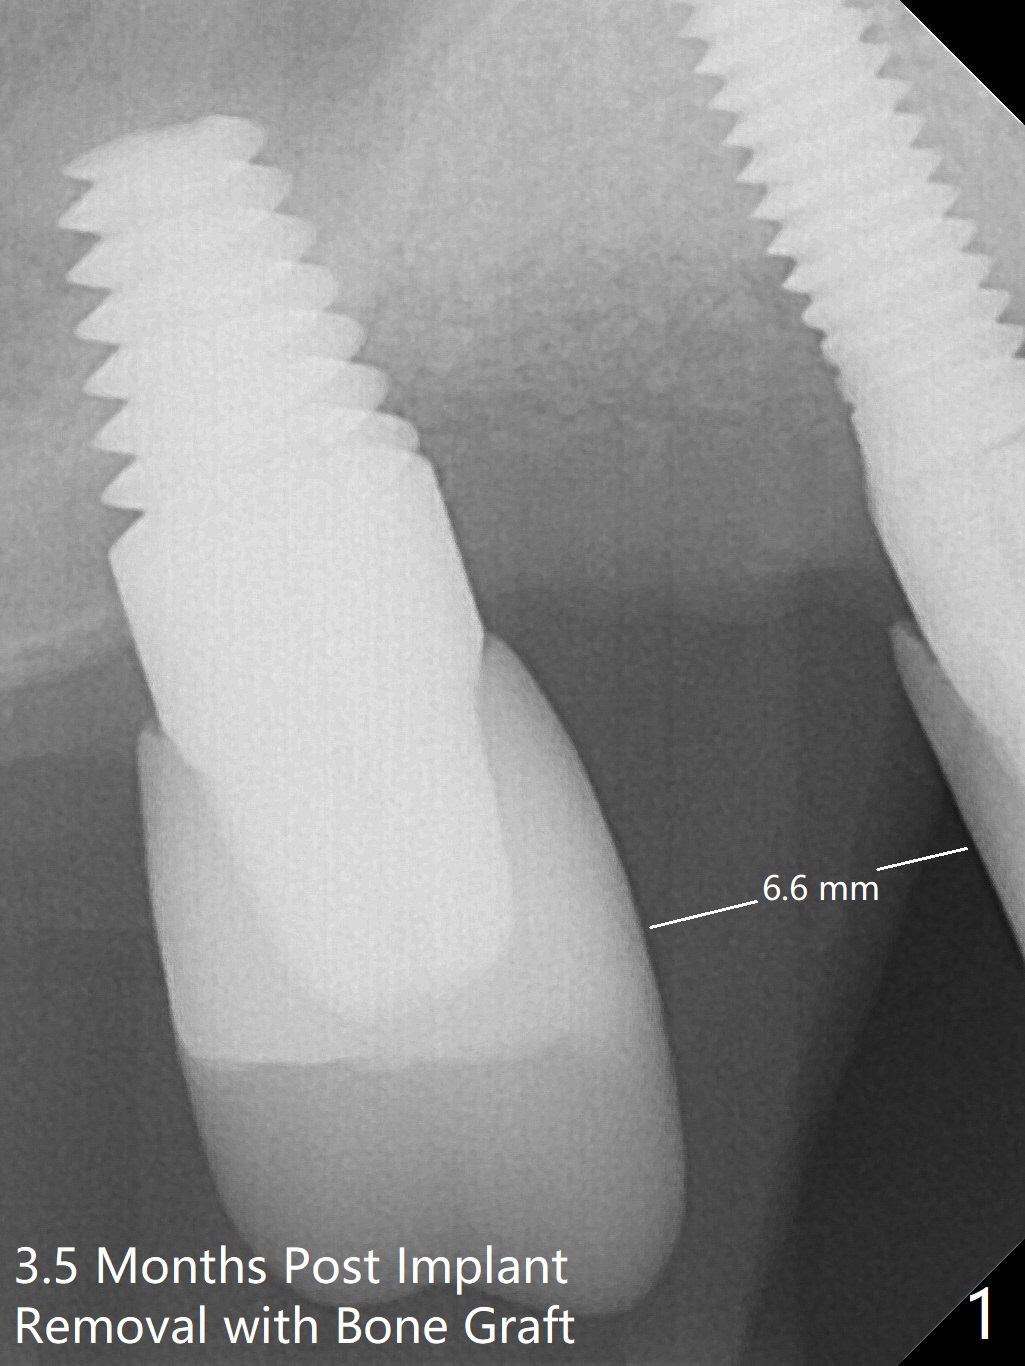

The osteotomy gap at #4 disappears 3.5 months post implant removal with bone graft; the mesiodistal space is 6.6 mm (Fig.1). Incision confirms disappearance of the osteotomy gap. A new osteotomy is established for 10 mm (Fig.2). A 2.5x10(4) mm 1-piece implant is placed with <50 Ncm; since the trimmed implant threads at #5 are exposed (Fig.3), Vanilla graft with Osteogen is placed mesial and distal to the new small implant (Fig.4 *). There is no bone loss 3.5 months postop (Fig.5,6). After cementation of the crown (Fig.7 C) with the thin abutment (*), the patient feels that the crown has mobility. The crown in fact has no clinical mobility; it cannot be removed. After occlusal equilibrium, the patient does not feel the same. The thin 1-piece implant must flex under heavy occlusion. The patient is a bruxer. There is no crestal bone resorption 4 months post cementation (8 months post cementation, Fig.8,9). There is no sign of periimplantitis anymore. The implant remains mobile and symptomatic (chewing pain) 14 months post cementation (Fig.10). There is no bone loss 2 years 4 months post cementation (Fig.11).